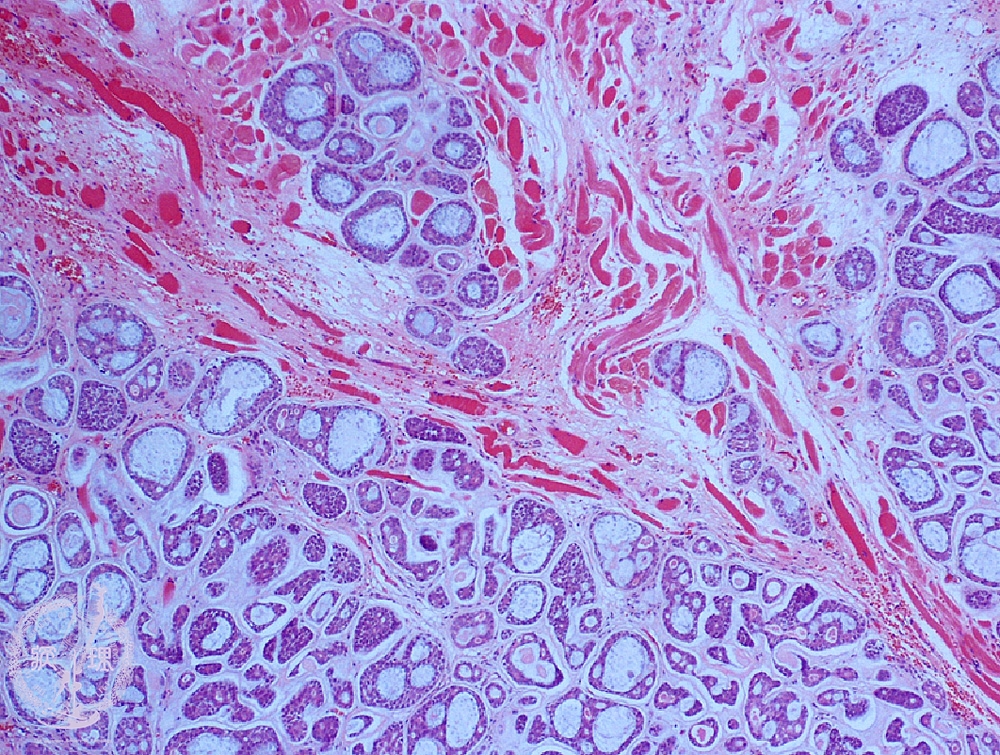

- (7)Salivary gland tumor(★adenoid cystic carcinoma)

Microscopic finding (HE stain, low-power view):Cribriform and tubular nests infiltrate into the muscle (*).